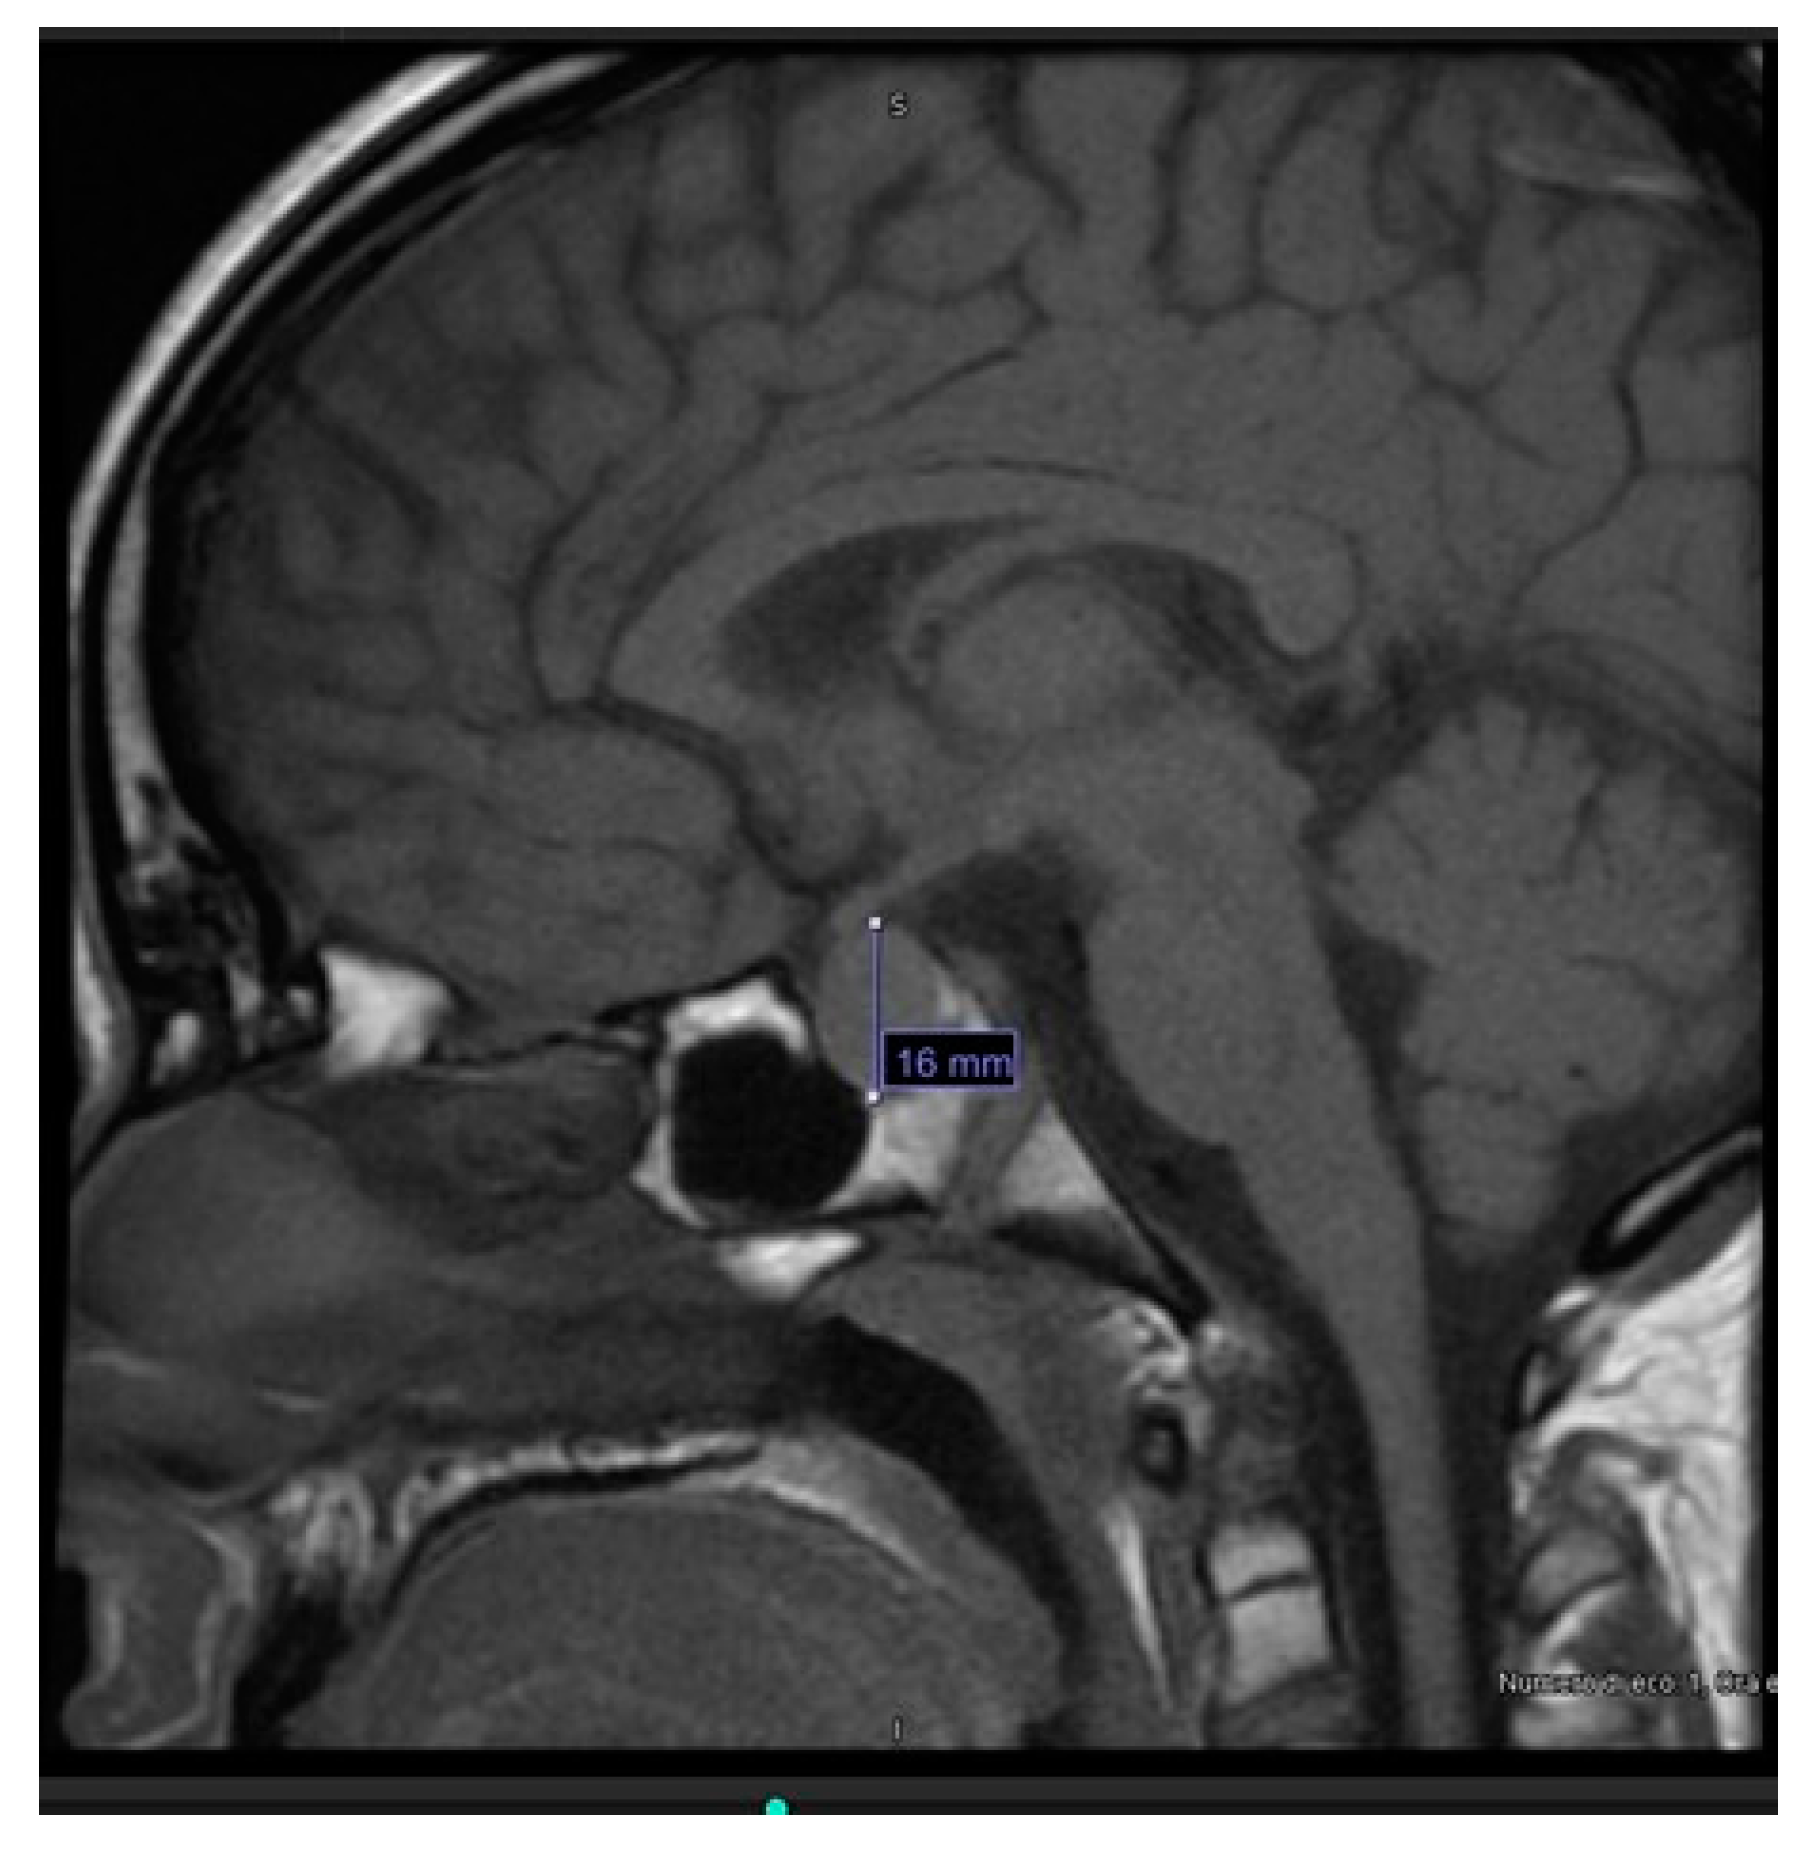

Considering the extreme elevation of TSH, according to the internal protocol, hypothalamic-pituitary magnetic resonance imaging (MRI) was performed and revealed pituitary hyperplasia (diameters of 16 × 12 × 16 mm, with convex upper margin) (Figure 3).

During hospitalization, the patient’s clinical status showed progressive improvement, the edema regressed and the pericardial effusion decreased to 4 mm. At discharge, after 2 weeks, FT4 levels had increased (6.3 pg/mL), while TSH levels (610.9 μ IU/mL) and creatinine (0.99 mg/dL) had decreased. Levothyroxine dose at discharge was 75 mcg and 100 mcg every other day. 3 weeks after diagnosis, FT4 was in range (11.1 pg/mL). After 2 months, TSH (1.02 μ IU/mL) and creatinine (0.61 mg/dL) also normalized, and prolactin levels decreased significantly (36.2 ng/mL). MRI at 6 months showed resolution of the pituitary hyperplasia, with height reduced from 16 to 3.5 mm. Growth assessment revealed high growth velocity at 6 months (11.6 cm/year) and in the first year of treatment (14.6 cm/year).

In our patient, MRI, performed in accordance with the Center’s internal protocol for patients with very high TSH levels, detected a pituitary hyperplasia. The true incidence of this condition remains largely unknown because MRI is not routinely indicated in the diagnostic pathway of primary hypothyroidism, and it may remain radiologically undocumented. The pathogenesis of pituitary hyperplasia in severe long-standing primary hypothyroidism is explained by the reduction of circulating thyroid hormones. It leads to loss of the negative feedback on hypothalamus, with consequent excessive secretion of thyrotropin-releasing hormone (TRH) and proliferation of thyrotropic cells, leading to compensatory hyperplasia [12]. Enlargement of the pituitary gland in these patients can be very pronounced, even with suprasellar extension; however, unlike pituitary tumors or craniopharyngioma, it rarely causes signs or symptoms. Instead, it regresses with levothyroxine treatment and usually does not require surgery [12].

Figure 3. MRI of pituitary hyperplasia.